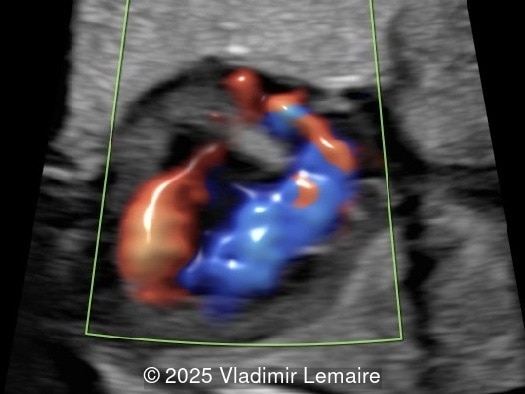

We present a case of isolated tricuspid atresia type 1 with persistent left superior vena cava. No other extracardiac anomalies were found. Our diagnosis was confirmed after birth.

In the images below, the abbreviations are as follows: RA: right atrium; RV: right ventricle; LV: left ventricle; MV: mitral valve; LA: left atrium; FO: foramen ovale; SVC: superior vena cava; LSVC: left superior vena cava; PV: pulmonary veins; PA: pulmonary artery; MPA: main pulmonary artery; RPA: right pulmonary artery; AO: aorta; dAO: descending aorta; aAO: ascending aorta; DA: ductus arteriosus; T: trachea; * marks the ventricular septal defect.

Color Doppler confirms the diagnosis on grayscale ultrasound, as it demonstrates the lack of blood flow across the tricuspid valve and a patent mitral valve. Due to increased blood flow across the mitral valve, aliasing is typically noted on color Doppler. Mitral valve regurgitation has been associated with a poor outcome. The right ventricular cavity is filled in late diastole from the left ventricle, through the ventricular septal defect. Left-to-right shunting across the ventricular septal defect can be seen on color Doppler. Color Doppler is helpful in the evaluation of flow across the great arteries. Flow across the pulmonary artery is generally antegrade. Pulmonary stenosis should be suspected when the vessel is diminutive in size rather than the demonstration of turbulent flow on color Doppler, which is typically absent in these cases.